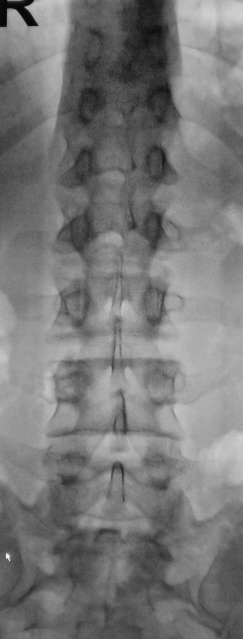

От невролога.

Приложения:

0.p5050041a.jpg0.p5050043a.jpg0.p5050044a.jpg

Можно норму писать?